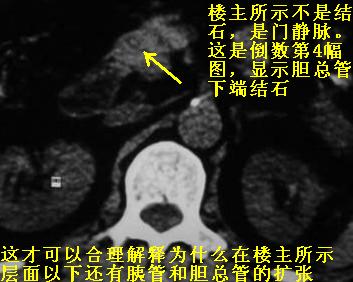

劳烦各位老师看一下最后一幅箭头指的地方是不是胆总管结石.ct值约63hu.

感觉不是结石可能,与上一层面联系应该是门脉区影像,图像显示不佳,胆总管显示不清[特别是胰头以上段],目前影像只能说肝内外胆管扩张,胰管扩张,胆囊扩大。提示胆总管远端梗阻。可考虑肿瘤或结石所致

胆总管下端结石

支持胆总管下段结石并肝内外胆管扩张。

楼主的箭头标的太棒了,不看最后一副图,我都没看到胆管下端有问题,象结石